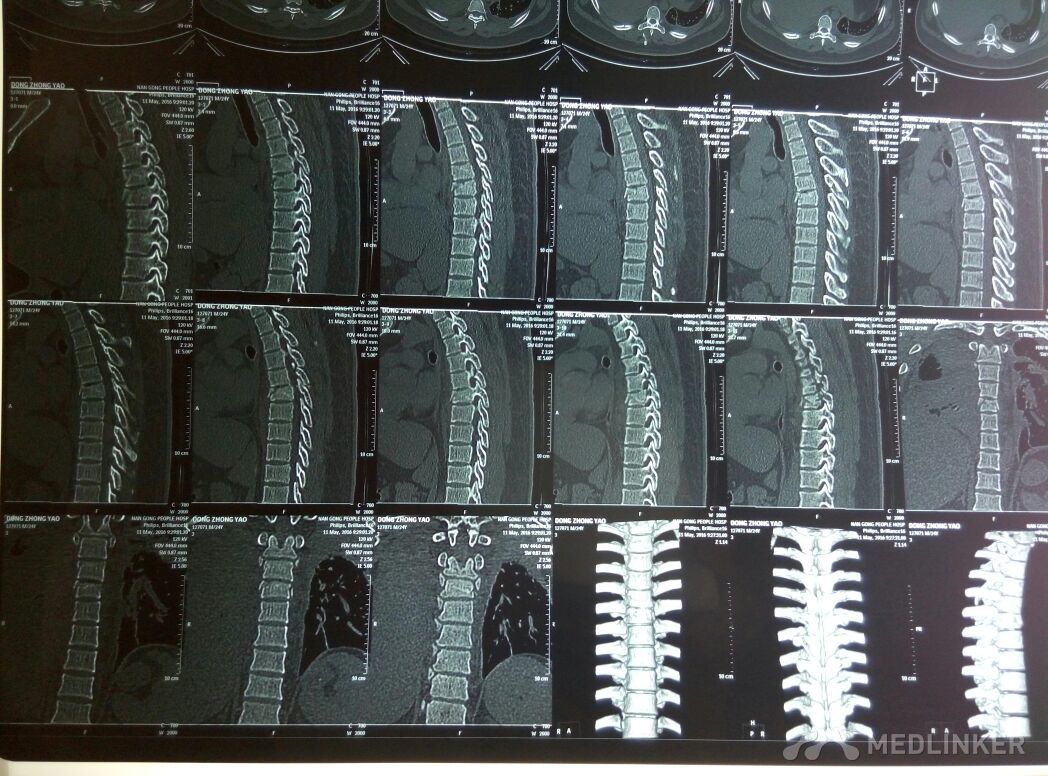

各位老师看看这种情况需不需要手术治疗!?

胸椎骨折,无神经损伤症状,各位老师指点一下,看看需不需要手术治疗!